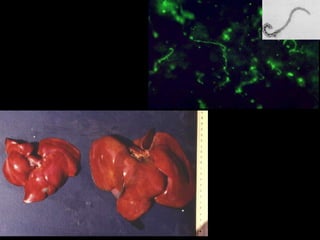

Exemplos de Icterícia Pós-Hepática Obstrução por parasitas Cirrose Colangites Cálculos Neoplasias

Exemplos de IcteríciaPós-Hepática Obstrução por parasitas Cirrose Colangites Cálculos Neoplasias

Estudar o significadode: Cirrose Colangite Colecistite Fasciola hepatica Platynosomum spp Cálculo biliar